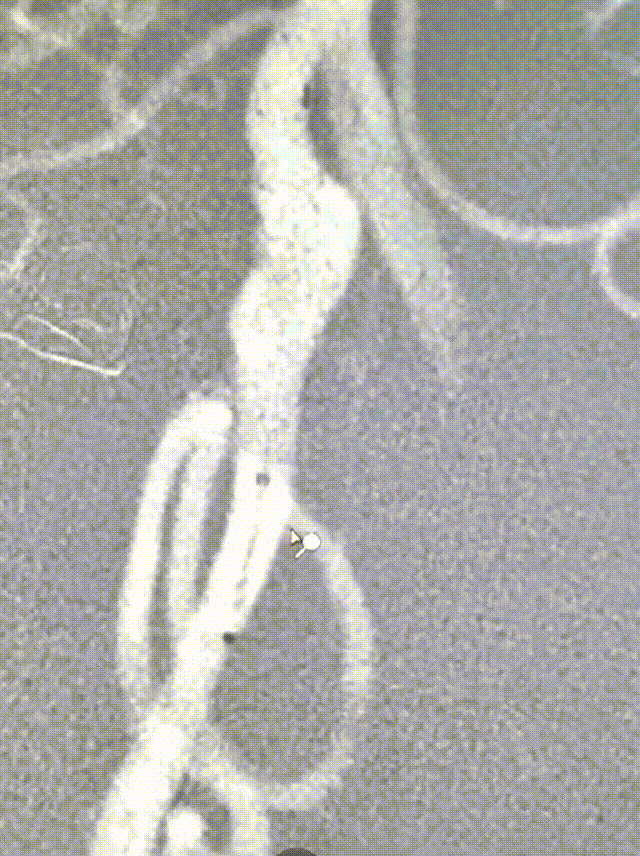

将EasyRadial™输送导管送至V3段保持支撑。

造影测量血管直径3.5,选择4.0*30mm 密网支架释放。

密网支架释放完毕造影,显示支架打开良好。